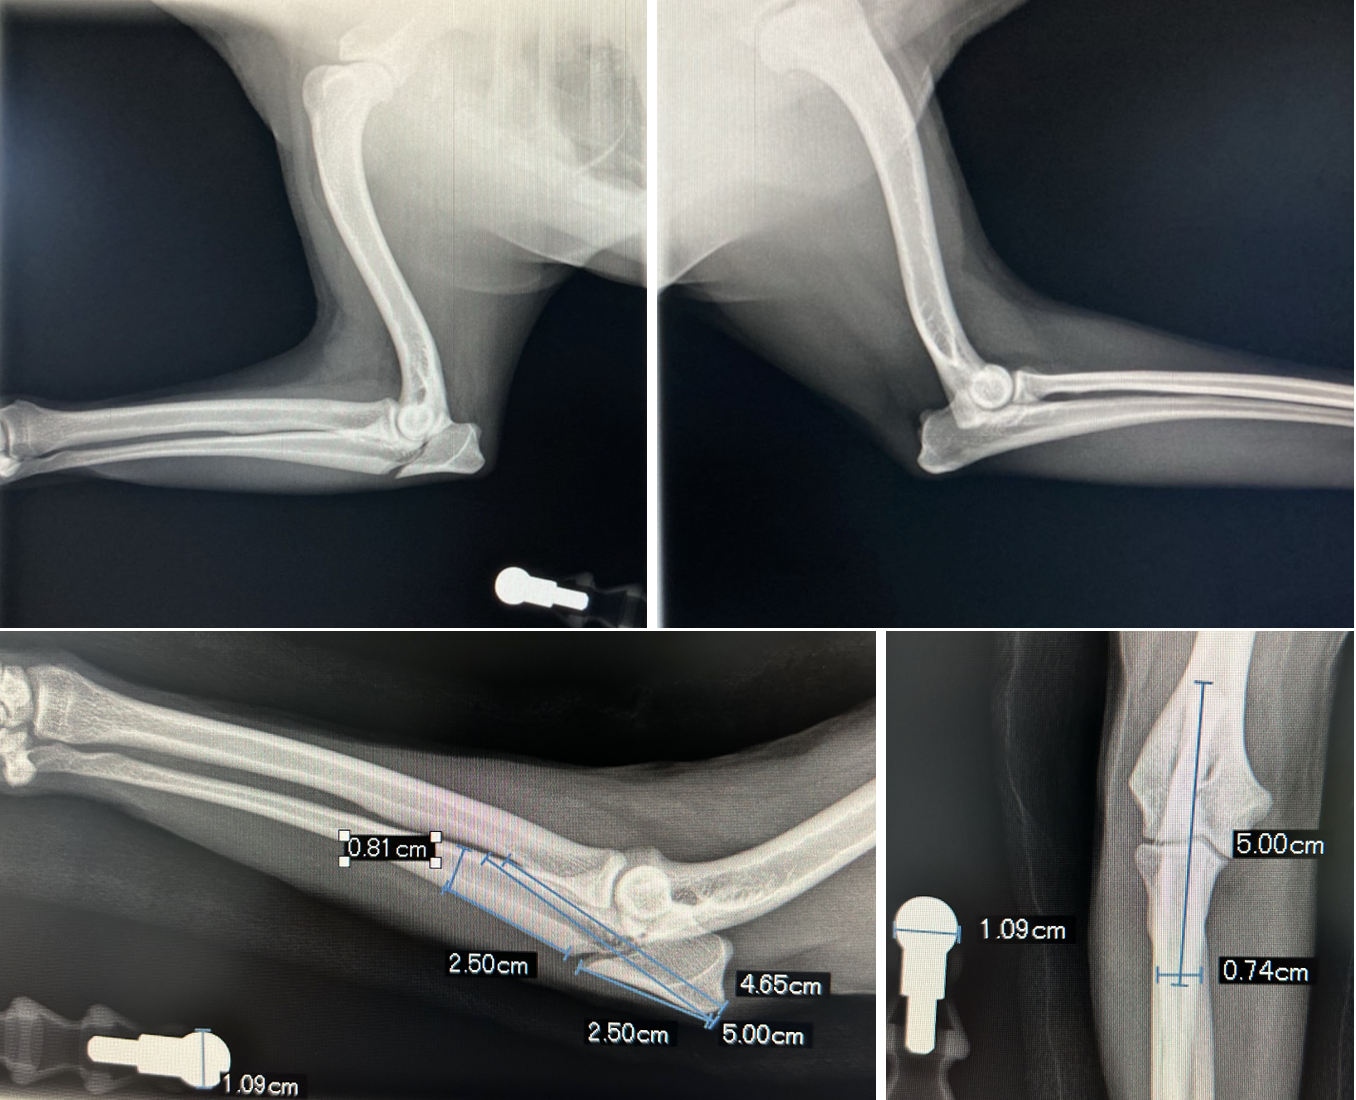

右肘頭骨折

診断と治療

髄内ピン、テンションバンドワイヤーによる固定

before